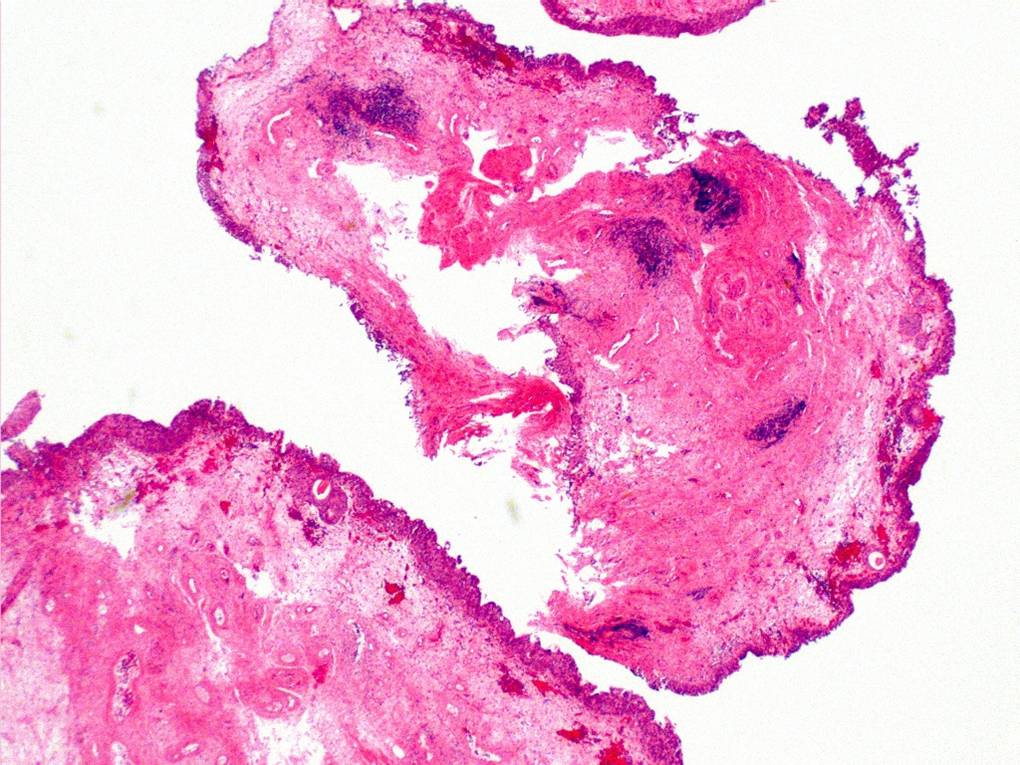

Bladder Flat Lesions

Case ID: 73